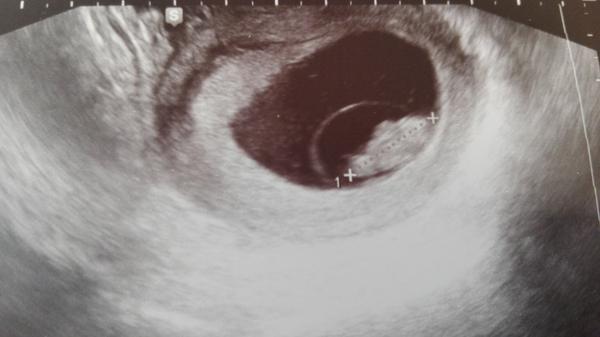

Ahojte akurát idem od lekára, na sone bilo srdiečko, maličké má 5,5 mm, zatiaľ všetko OK, iba má trápia strašné nevoľnosti. Mám prísť ešte na kontrolné sono o 2 týždne. Dostala som aj duphaston pre istotu.

Ahojte, včera som bola na kontrolnom sone, drobec pekne rastie už má 1.9 CM srdiečko bije, všetko zatiaľ OK až na strašné celodenné nevoľnosti, najhoršie je to večer, našťastie jedlo zo mňa ide von minimálne chodím do práce, za PC vládzem sedieť aj gauč máme v kancelárii. Kolegovci aj šéf vychádzajú v ústrety vo všetkom. Prvá poradňa o 2 týždne.